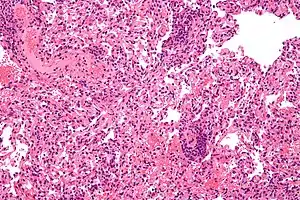

| Micrograph showing lung transplant rejection. Lung biopsy. H&E stain. | |

Developing with formation of cellular immunity, acute rejection occurs to some degree in all transplants, except between identical twins, unless immunosuppression is achieved (usually through drugs). Acute rejection begins as early as one week after transplant, the risk being highest in the first three months, though it can occur months to years later. Highly vascular tissues such as kidney or liver often host the earliest signs—particularly at endothelial cells lining blood vessels—though it eventually occurs in roughly 10 to 30% of liver transplants, and 10 to 20% of kidney transplants. A single episode of acute rejection can be recognized and promptly treated, usually preventing organ failure, but recurrent episodes lead to chronic rejection. It is believed that the process of acute rejection is mediated by the cell mediated pathway, specifically by mononuclear macrophages and T-lymphocytes. Histology of acute rejection is defined by dense lymphocytic cellular infiltrate as well as vasculitis of organ donor vessels.

Chronic rejection explains long-term morbidity in most lung-transplant recipients,[18][19] the median survival roughly 4.7 years, about half the span versus other major organ transplants.[20] In histopathology the condition is bronchiolitis obliterans, which clinically presents as progressive airflow obstruction, often involving dyspnea and coughing, and the patient eventually succumbs to pulmonary insufficiency or secondary acute infection.

Airflow obstruction not ascribable to other cause is labeled bronchiolitis obliterans syndrome (BOS), confirmed by a persistent drop—three or more weeks—in forced expiratory volume (FEV1) by at least 20%.[21] BOS is seen in over 50% of lung-transplant recipients by 5 years, and in over 80% by ten years. First noted is infiltration by lymphocytes, followed by epithelial cell injury, then inflammatory lesions and recruitment of fibroblasts and myofibroblasts, which proliferate and secrete proteins forming scar tissue.[22] Generally thought unpredictable, BOS progression varies widely: lung function may suddenly fall but stabilize for years, or rapidly progress to death within a few months. Risk factors include prior acute rejection episodes, gastroesophageal reflux disease, acute infections, particular age groups, HLA mis-matching, lymphocytic bronchiolitis, and graft dysfunction (e.g., airway ischemia).[23]

Rejection detection

Diagnosis of acute rejection relies on clinical data—patient signs and symptoms but also calls on laboratory data such as blood or even tissue biopsy. The laboratory pathologist generally seeks three main histological signs: (1) infiltrating T cells, perhaps accompanied by infiltrating eosinophils, plasma cells, and neutrophils, particularly in telltale ratios, (2) structural compromise of tissue anatomy, varying by tissue type transplanted, and (3) injury to blood vessels. Tissue biopsy is restricted, however, by sampling limitations and risks/complications of the invasive procedure.[25][26][27] Cellular magnetic resonance imaging (MRI) of immune cells radiolabeled in vivo might—similarly to Gene Expression Profiling (GEP)—offer noninvasive testing.[28][29]